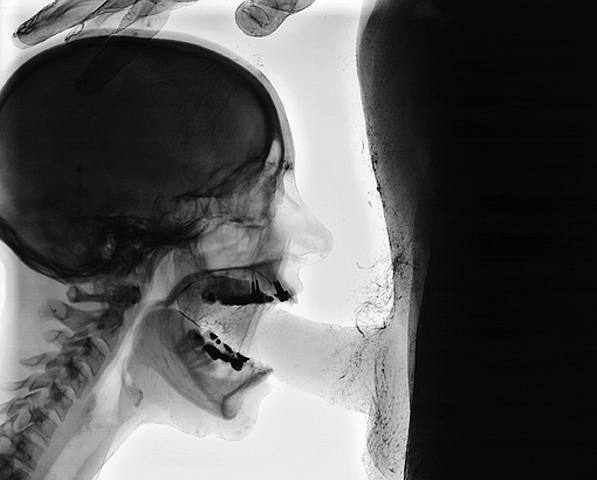

Here is what the photo looks like with the grey scale inverted. Looks more like an actual x-ray. The image(s) are still not correct as far as detail is concerned.